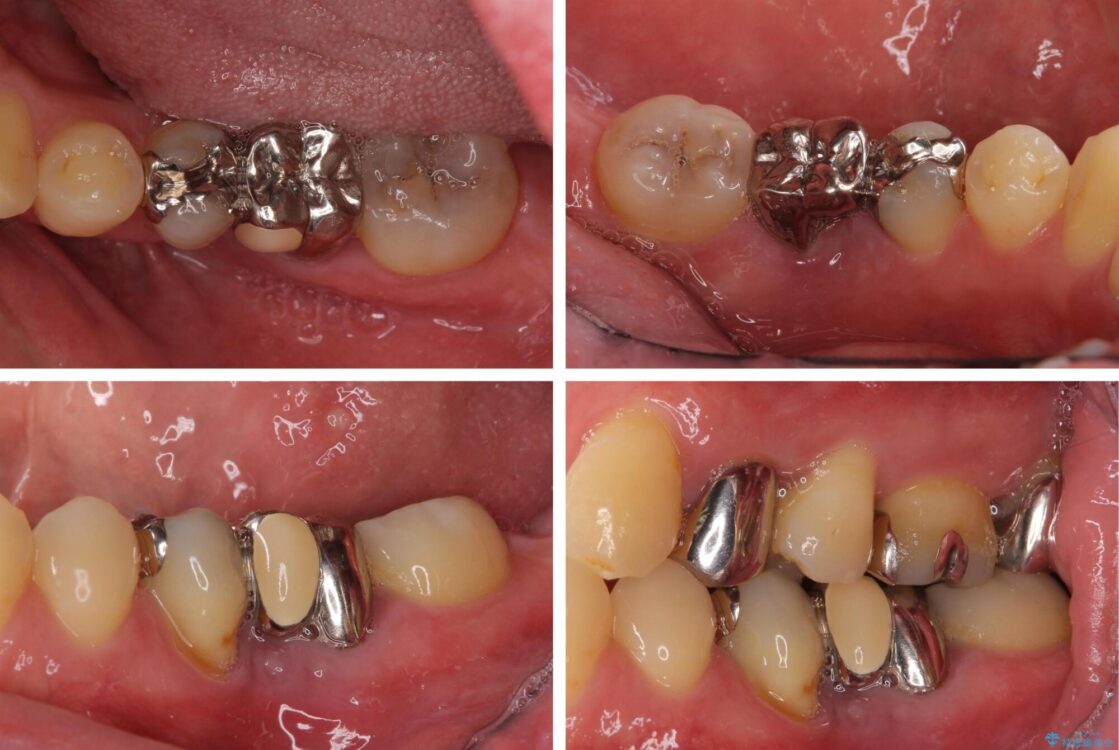

左右下顎の大臼歯は、ともに歯根が破折しており、抜歯が必要な状態でした。

放置したことで炎症による骨吸収が顕著であるため、骨造成を併用してインプラント埋入を行うこととしました。

矯正治療でインプラント埋入を行い、矯正治療後に気になる前歯と合わせてオールセラミッククラウンによる補綴治療を行うこととしました。

骨造成や歯肉移植など、治癒期間の長い処置を必要としたため治療期間は長くなりましたが、安定した咬み合わせと整った歯列となり、患者様には大変満足していただきました。

治療途中